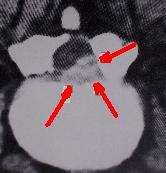

CT scan of laminectomy showing scar formation (highlighted in red)causing new stenosis.

Spinal stenosis can be a late complication after laminectomy for disc herniation or when surgery was performed for the primary pathologic condition of spinal stenosis.[8][73][74] In the Maine Study, among patients with lumbar spinal stenosis completing 8- to 10-year follow-up, low back pain relief, predominant symptom improvement, and satisfaction with the current state were similar in patients initially treated surgically or nonsurgically. However, leg pain relief and greater back-related functional status continued to favor those initially receiving surgical treatment.[75]

A large study of spinal stenosis from Finland found the prognostic factors for ability to work after surgery were ability to work before surgery, age under 50 years, and no prior back surgery. The very long-term outcome (mean follow-up time of 12.4 years) was excellent-to-good in 68% of patients (59% women and 73% men). Furthermore, in the longitudinal follow-up, the result improved between 1985 and 1991. No special complications were manifested during this very long-term follow-up time. The patients with total or subtotal block in preoperative myelography achieved the best result. Furthermore, patients with block stenosis improved their result significantly in the longitudinal follow-up. The postoperative stenosis seen in computed tomography (CT) scans was observed in 65% of 90 patients, and it was severe in 23 patients (25%). However, this successful or unsuccessful surgical decompression did not correlate with patients' subjective disability, walking capacity or severity of pain. Previous back surgery had a strong worsening effect on surgical results. This effect was very clear in patients with total block in the preoperative myelography. The surgical result of a patient with previous back surgery was similar to that of a patient without previous back surgery when the time interval between the last two operations was more than 18 months.[76]

Post-operative MRI findings of stenosis are probably of limited value compared to symptoms experienced by patients. Patients' perception of improvement had a much stronger correlation with long-term surgical outcome than structural findings seen on postoperation magnetic resonance imaging. Degenerative findings had a greater effect on patients' walking capacity than stenotic findings [77][78]

Postoperative radiologic stenosis was very common in patients operated on for lumbar spinal stenosis, but this did not correlate with clinical outcome. The clinician must be cautious when reconciling clinical symptoms and signs with postoperative computed tomography findings in patients operated on for lumbar spinal stenosis.[79]

A study from Georgetown University reported on one-hundred patients who had undergone decompressive surgery for lumbar stenosis between 1980 and 1985. Four patients with postfusion stenosis were included. A 5-year follow-up period was achieved in 88 patients. The mean age was 67 years, and 80% were over 60 years of age. There was a high incidence of coexisting medical diseases, but the principal disability was lumbar stenosis with neurological involvement. Initially there was a high incidence of success, but recurrence of neurological involvement and persistence of low-back pain led to an increasing number of failures. By 5 years this number had reached 27% of the available population pool, suggesting that the failure rate could reach 50% within the projected life expectancies of most patients. Of the 26 failures, 16 were secondary to renewed neurological involvement, which occurred at new levels of stenosis in eight and recurrence of stenosis at operative levels in eight. Reoperation was successful in 12 of these 16 patients, but two required a third operation. The incidence of spondylolisthesis at 5 years was higher in the surgical failures (12 of 26 patients) than in the surgical successes (16 of 64). Spondylolisthetic stenosis tended to recur within a few years following decompression. Because of age and associated illnesses, fusion may be difficult to achieve in this group.[80]